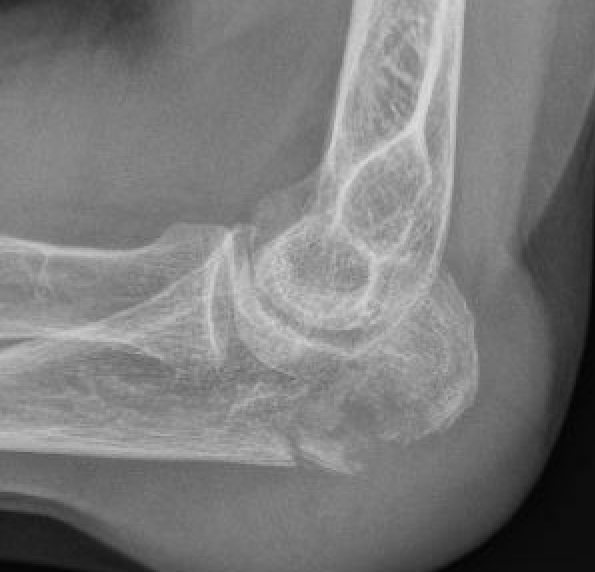

Mayo Classification

A: Non comminuted

B: Comminuted

| Type I | Type II | Type III |

|---|---|---|

| Minimally displaced | Displaced | Trans-olecranon fracture dislocation |

| 10% | 85% | 5% |